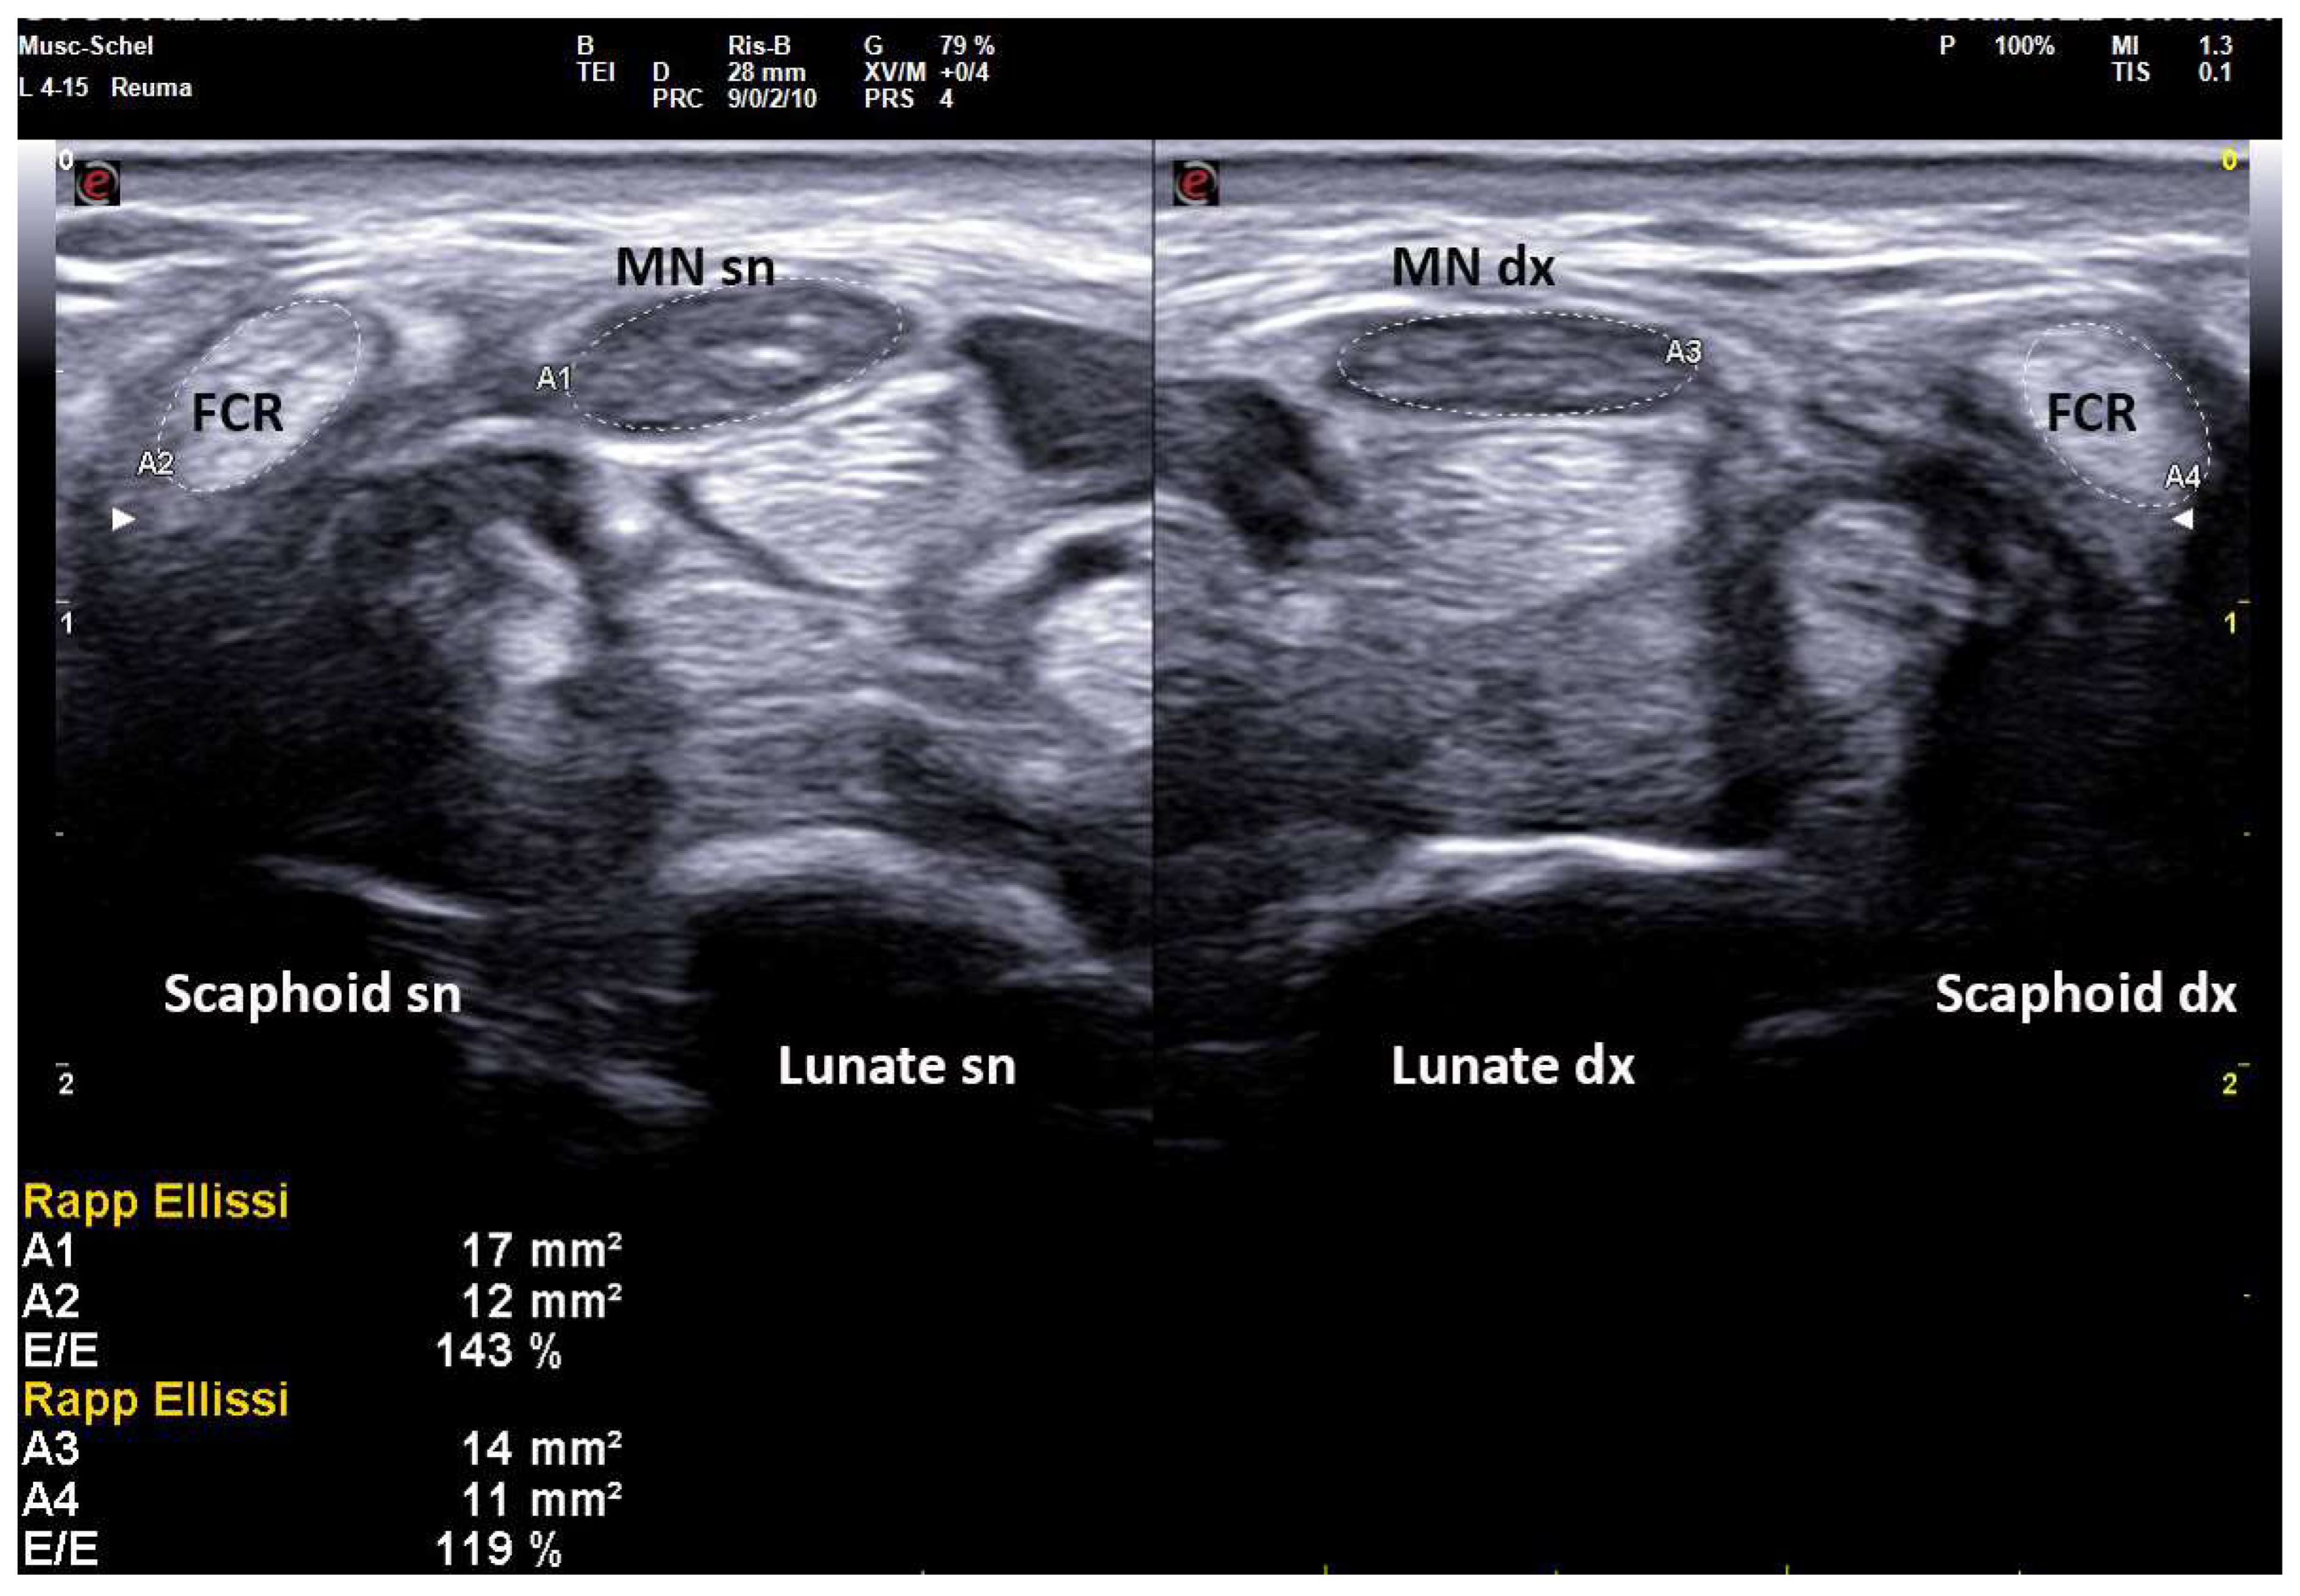

On the same day of EDS, every patient underwent a high-resolution US examination (4–15 MHz and 8–24 MHz linear probes, MyLab X8 eXP Esaote and 6–18 MHz linear probe, MyLab Twice, Esaote, Genoa, Italy) of the carpal tunnel in the Rheumatology Unit of the same hospital. The examination was performed by a single rheumatologist with 20 years of experience in musculoskeletal US and blinded to clinical and electrophysiologic CTS severity. Patients were seated in a chair with arms extended, hands resting in a horizontal supine position and fingers relaxed. The median nerve cross-sectional area (CSA) was measured at the tunnel inlet (just before the proximal margin of the flexor retinaculum) by tracing the inner border of the thin hyperechoic rim of the nerve (perineurium) with the automatic ellipsoid technique (or manual tracing technique if the nerve had an irregular shape). Moreover, the CSA of flexor carpi radialis (FCR-CSA) was measured over (or just proximal to) the scaphoid tubercle, where the tendon runs parallel to the skin (possibly in the same scan of MN-CSA, with the automatic ellipsoid technique). The ratio between the two CSAs was calculated and recorded as the nerve tendon ratio (NTR) (expressed as a percentage) (Figure 2). The probe was applied without additional pressure, and the mean value of three measurements, along with clinical and anthropometric characteristics (weight, height, wrist circumference), was recorded.

Figure 2.

Transverse scan over left and right carpal tunnels in male patient (172 cm × 82 kg, 18.5 cm of wrist circumference) affected with extremely severe CTS (Padua Scale 5 bilaterally). Linear 4–15 MHz probe. Both MN-CSA show frankly pathologic values (Area 1, left: 17 mm2, Area 3, right: 14 mm2). NTR is calculated as the ratio between MN-CSA and FCR-CSA (expressed as a percentage), and shows bilaterally pathologic values (left 143%, right 119%) indicative for severe CTS. MN = median nerve, FCR = flexor carpi radialis.